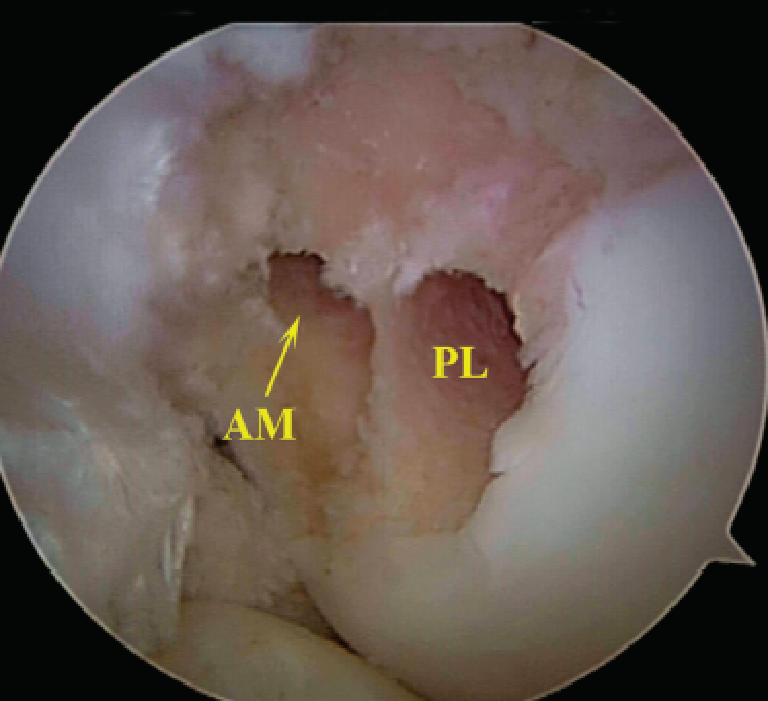

关节镜下观

正常前交叉韧带

前交叉韧带损伤后形成的疤痕组织

胎儿膝关节显示:两个功能束(AM,PL)

关节镜显示AM,PL